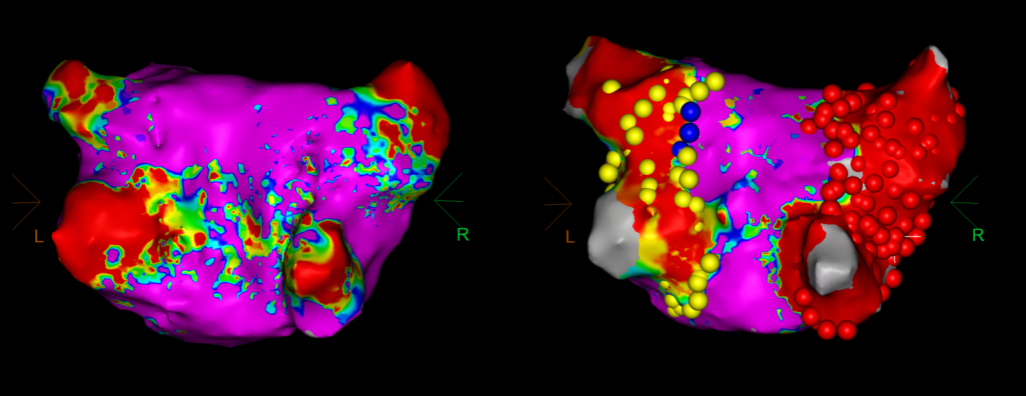

手术在介入导管室的通力配合下进行,姜馨主任、薛建颖主治医师、刘成峰医师密切配合,术中通过右侧股静脉送入心腔内超声(ICE)至右心房,排除左房血栓后成功指导精准房间隔穿刺,沿可调弯鞘管送入锦江心脏脉冲电场消融导管至左房,构建左房三维解剖模型并行基质标测,标测显示左房基质尚可,分别行左侧、右侧肺静脉消融。消融参数:1800v、400ms、400μs,共放电消融148次(消融左上肺静脉时转复为窦性心律),验证双肺静脉均隔离。术后重新标测显示所有肺静脉均已急性阻滞,消融效果理想,肺静脉前庭损伤范围也达到了预期的标准,同时ICE监测未见明显心包积液。手术仅用时30分钟,时间明显缩短,手术过程精准高效。术后患者恢复情况良好并顺利出院。术后1月复查心电图提示窦性心律,心脏超声提示心脏较前明显缩小,收缩功能明显改善,射血分数由25%提升至40%,心功能标记物NT-proBNP 恢复正常,仅54pg/ml。

图4 PFA于左上肺静脉消融时转为窦率,继续消融

图5 消融前后基质标测提示肺静脉消融效果明显